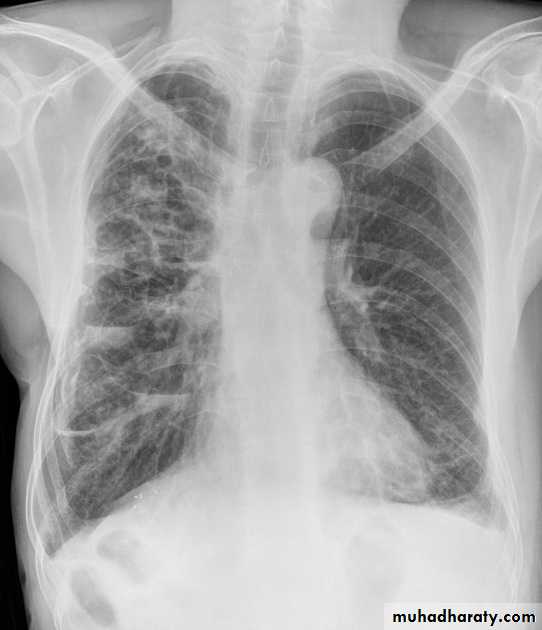

1.patchy consolidation or poorly defined linear and nodular opacities in both apices , upper zone in one lung , & lower zone in other lung ( ulternating lesion ) .2. Post-primary infections are far more likely to cavitate with multiple abscess formation & air fluid level more develop in the posterior segments of the upper lobes.

3. Tuberculomas seen in post-primary TB and appear as a well defined rounded mass typically located in the upper lobes .

4. Miliary tuberculosis is uncommon but carries a poor prognosis. It represents haematogenous dissemination of an uncontrolled tuberculous infection. It is seen both in primary and post-primary tuberculosis. Although implants are seen throughout the body, the lungs are usually the easiest location to the image. Miliary deposits appear as 1-3 mm diameter nodules . are uniform in size and uniformly distributed